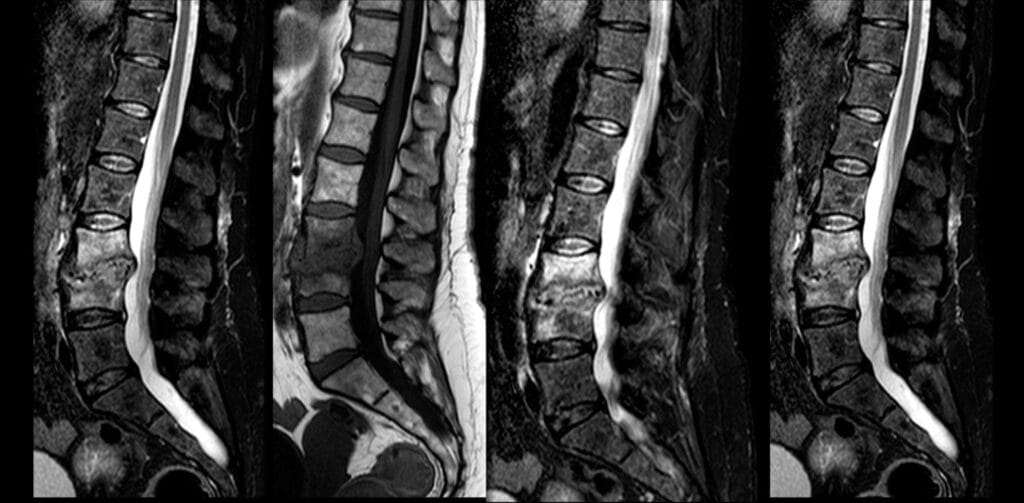

La espondilodiscitis, también conocida como osteomielitis vertebral, es de acuerdo a los Institutos Nacionales de Salud de Estados Unidos (NIH por sus siglas en inglés), una enfermedad rara con una tasa del 3 - 5% que se caracteriza por la infección en uno o varios discos intervertebrales, sin embargo, y como la literatura lo indica, a pesar de ser una enfermedad rara, es la tercera forma más común de osteomielitis en adultos mayores a 50 años.

Un estudio publicado en Springer Nature evaluó el uso de este enfoque en 13 pacientes tratados entre 2022 y 2024. Los pacientes fueron sometidos a una biopsia osteodiscal percutánea y colocación intradiscal e intravertebral de una pasta de sulfato de calcio (STIMUAN) cargada con antibióticos.

Los resultados demostraron una tasa de éxito del 100% sin complicaciones mayores y una mejoría clínica evidenciada por la reducción del dolor en la puntuación de la escala EVA (de 8.2 inicial a 3.5 a los 12 meses) y disminución de los marcadores inflamatorios (de 7,35 a 0,23).

Estos hallazgos sugieren que el uso de STIMULAN representa una alternativa segura y eficaz para la administración local de antibióticos y ser parte del tratamiento de la espondilodiscitis.